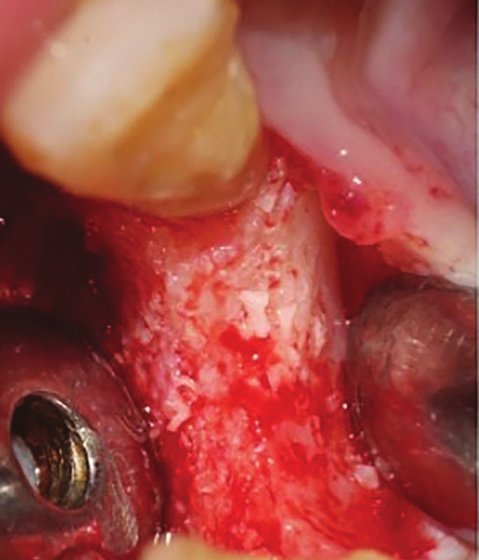

Figure 14: Combination of bovine bone and PRF (Sticky bone).

A 33 years-old male patient was visiting our clinic to replace missing teeth no 7 and 8. He was medically fit and mentioned that his teeth were lost due to car accident few years back. Intraoral examination shows absence of space for implant placement and restoration, orthodontic treatment was conducted for 18 sessions followed by surgical implant placement after stabilization of the occlusion. Following the restoration of the space, the amount of horizontal bone loss was evident both clinically and on CAT examinations (Fig.10, 11). A linear incision with mucoperiosteal flap elevation were conducted, the amount of horizontal bone loss was advanced (Fig. 12), which was an indication for autologous bone graft, patient refused to undergo an invasive surgery so PRF associated bovine bone was planned in the area. Blood withdrawal and centrifugation were done with preparation of both L-PRF membranes and sticky bone (bovine bone associated PRF) (Fig.13, 14,15). The combination was placed on the host bone deficiency and covered by a first layer of L-PRF membranes in order to stabilize the graft and insure hemostasis, the second layer of L-PRF membranes covered the cross linked collagen membrane placed in the same area and covering the first entity (Fig.16).